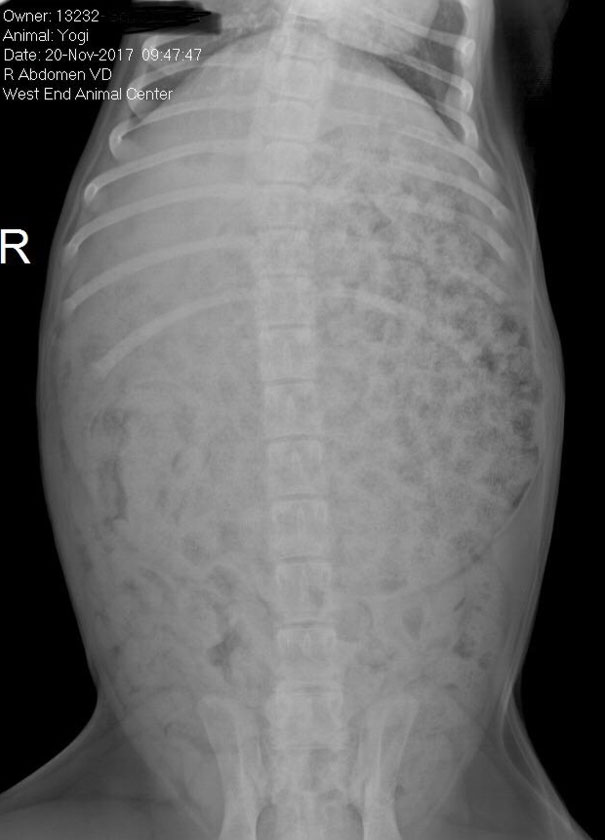

我家拉布拉多偷吃了一个食品包装袋,送到医院花了我250美金……还好最终狗没事,这张片子就留作纪念了。